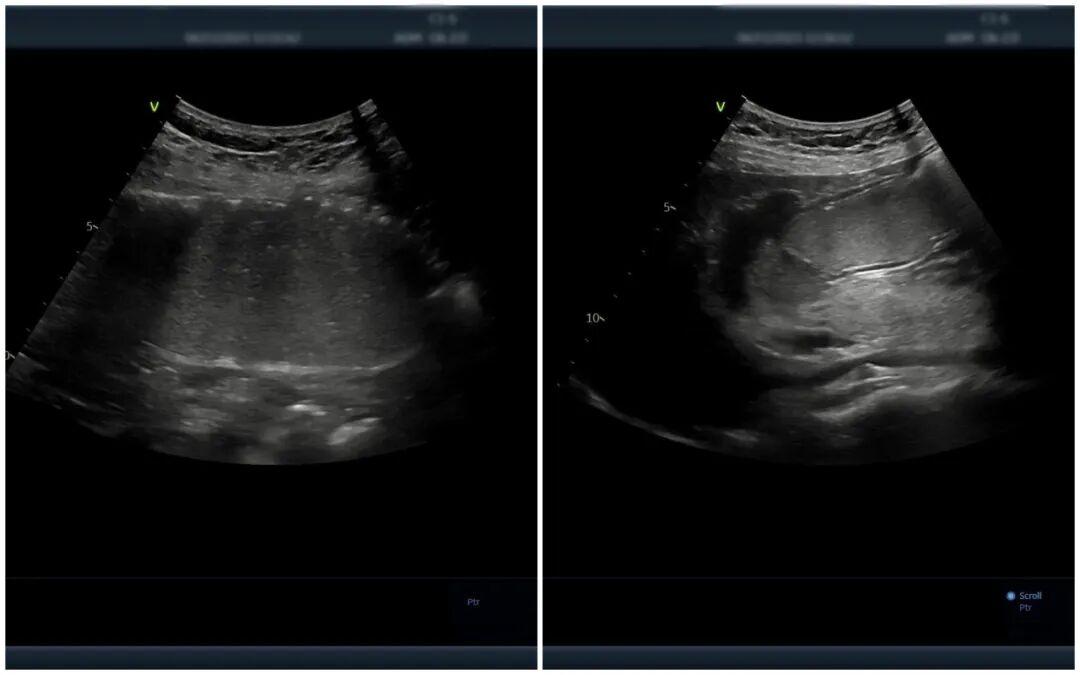

△胃肠超声造影提示:黏膜层毛糙,元鼎证券_元鼎证券APP下载安装_在线股票配资平台回声减低,胃壁呈局限性增厚,符合慢性胃炎声像图特征

简单来说,就是患者在空腹8小时后,喝下一杯香甜顺滑、形似“糊糊”的胃肠超声造影剂,以此充盈胃腔和十二指肠,有效排除胃肠道内的气体,形成优良的“透声窗”。随后,超声医师通过超声设备,可清晰观察到胃壁和肠壁的层次结构、厚度变化、蠕动状态以及周围毗邻脏器的情况,就像给胃肠道做了一次“B超”,轻松便捷。